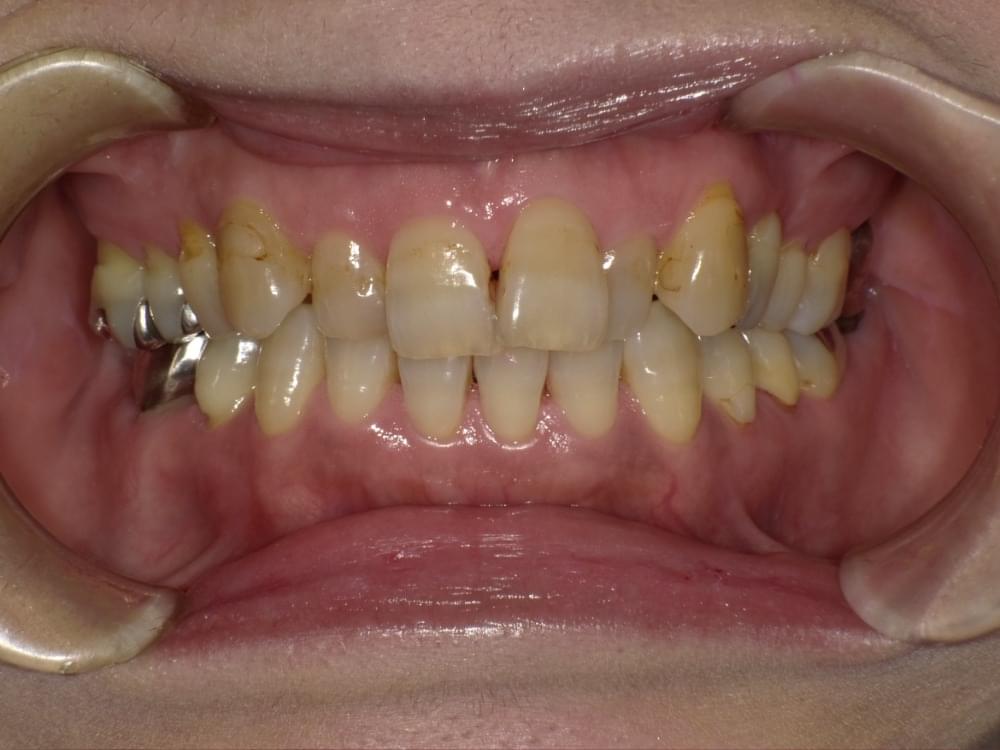

歯周病予防の為にセラミック装着を間違えると大変!!

こちらの写真の患者さんは上下前歯に沢山のセラミックをいれた直後から歯ぐきが良くならないとの理由で来院されました。

多くの時間をさいて歯ブラシとデンタルフロスをして頂いておりますが改善されておりません。

その原因は装着したセラミックにありました。

原因

① レントゲンで見るとセラミックが自分の歯よりも大きい

② 自分の歯とセラミックの境目にすき間が開いている

下矢印

③ ①と②の結果としていくら磨いても歯垢(プラーク)が取り除けない。